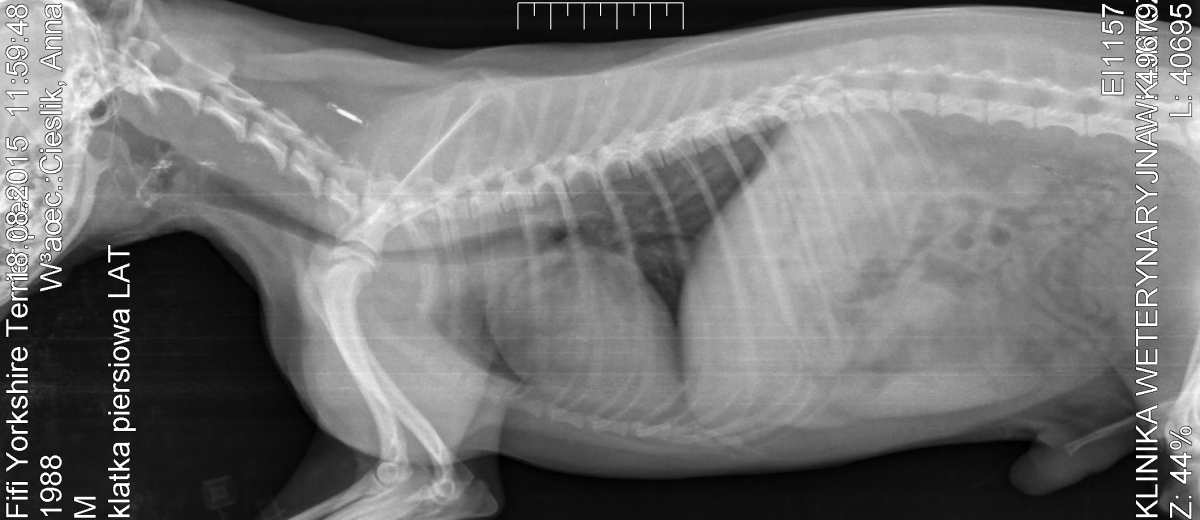

4. Witam serdecznie to mój pierwszy post na tym forum. Nasz piesek to 7 letni yorkshire terrier mieszkamy zagranicą gdzie w porównaniu do Polski weterynarze są strasznie zacofani nasz pies 2 miesiące temu zaczął sikać krwią pojechaliśmy odrazu do weta który zbadał psa palcem przez odbyt i stwierdził przerośniętą prostatę , dał antybiotyk i kazał po 5 dniach wrócić na kastracje! Twierdził że badanie USG czy krwi jest zbędne bo diagnoza jest już postawiona ,wiec wróciliśmy po tygodniu i go wykastrowaliśmy piesek czuje się już świetnie mogę nawet powiedzieć że ma więcej energii niż przez zabiegiem i biega jak szalony gdzie nigdy wcześniej tak się nie cieszył z biegania. Korzystając z okazji że odwiedziliśmy Polskę postanowiliśmy z żoną ze zrobimy szczegółowe badania naszego pupila bo od zawsze miał problemy z tchawicą kaszle i dusi w trakcie ekscytacji lub przy dużym wysiłku i też czasem miewa bóle brzuszka. Po badaniu endoskopowym padła diagnoza zapad tchawicy w odcinku szyjno piersiowym III stopnia oraz silne zapalenie tchawicy. Wet wykonał też RTG i tu się podłamaliśmy bo z RTG wynika ze pies ma: *Powiększone serce (w odsłuchu były delikatne szmery nad zastawka P/K lewą) *Powiększona wątroba (do tej pory karmiliśmy go karma z Tesco gdzie była duża zawartość tłuszczu i pewnie odpadów również dostawał wszystko ze stołu na co miało chote) teraz jest na ścisłej diecie puszki royal hepatic i sucha karma royal light z L karnityną *Woda w płucach (nie wiem czy to mogło być spowodowane tym ze pies nie był przyzwyczajony do tak wysokich temperatur jakie były w Polsce a byliśmy tydzień nad morzem i pies dużo szalał był przemęczony) Z badania USG wyszło * cysta na prostacie 11mm ( czy mamy się martwic tą cystą? dodam że była robiona biopsja jąder po kastracji i nie było komórek rakowych) *problem z nerkami * powiększona wątroba Z badań moczu wynikło ze pies ma dożo bakterii na co dostał antybiotyk Z badan krwi jakieś dwa wyniki były strasznie złe ale przyczyna było to że pies 1,5 dnia nic nie zjadł przez te upały i chyba poziom cukru był niski czy to normalne ze przy tych lekach pies ma większe pragnienie na wodę i apetyt? (encorton i ornitil) Jeśli czyta to jakiś weterynarz to bardzo proszę zerknąć na wyniki i napisać mi swoją opinie , zalecenia bo strasznie się martwimy o naszego pupila jest naszym członkiem rodziny i zrobimy wszystko aby mu pomóc wyzdrowieć. Czy leki które wet mu przypisał są odpowiednie i nie zaszkodzą np. sercu? Czy może pies powinien dostać dodatkowe leki na wątrobę? Ufamy naszemu wetowi ale tak nas zmartwiła że postanowiliśmy napisać tu na forum. Przepraszam zę tak chaotycznie ten post napisałem ale za dużo tych chorób sie uzbierało. [attachment=16537:FIFI.PNG][attachment=16538:IMG_3365.JPG][attachment=16539:IMG_3366.JPG][attachment=16540:IMG_3367.JPG][attachment=16541:IMG_3368.JPG][attachment=16542:IMG_3369.JPG]